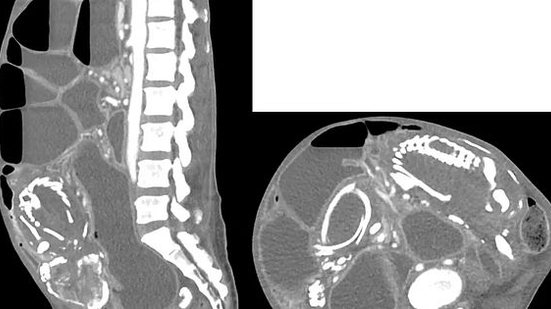

A mulher foi atendida com sintomas de dor e desconforto abdominal. Após exames, os médicos concluíram que a refugiada tinha um litopédio - ocorrência rara em que o feto morre e se calcifica dentro do corpo da gestante.

O litopédio é uma formação rara. Foram registrados menos de 300 casos desde 1582, quando um litopédio foi identificado na França. A palavra litopédio vem do grego e significa criança de pedra.